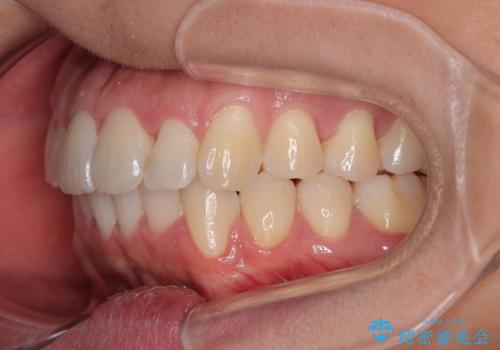

前方に捻れた前歯を治したい インビザライン矯正治療

- 前歯のデコボコを治したいとのことで来院された患者様です。

上下顎ともに歯列全体の後方移動とIPR(歯と歯の間を削る)によってデコボコが解消するように設計し、インビザラインにより治療を行うこととしました。

下顎前歯は後戻りを起こしやすいため、舌側を細いワイヤーで固定し、マウスピース型リテーナーで保定を行うこととしました。